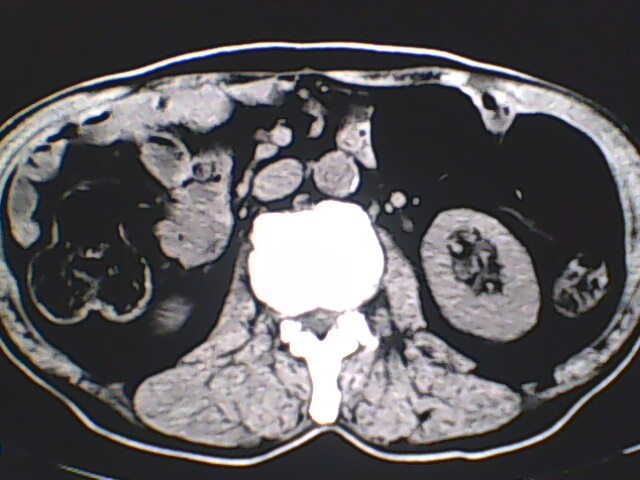

男,56岁,高血压,临床怀疑肾上腺问题,肝脏怎么那么高啊?能描述一下么?

右侧膈膨升,间位结肠,胸腰椎退行性骨关节病,右侧肾上腺可疑增生(图像颗粒太粗,窗太窄,不好看)。

支持 右侧膈膨升,间位结肠;胸腰椎退行性骨关节病;双侧肾上腺可疑增生。